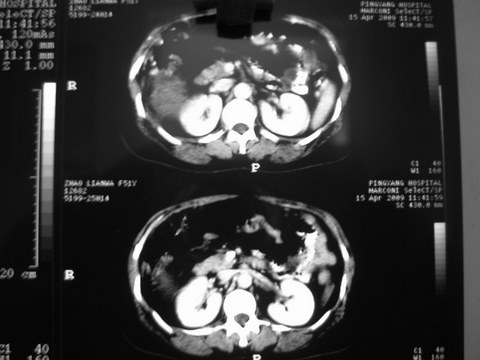

患者 女 51岁 两天前感觉上腹疼,无明显诱因,b超示肝右叶囊实性占位,边缘清楚,其内回声不均匀,ct增强如图,大家看看是什么 ,病人一年前及两月前b超检查只是提示胆囊炎

外院术后,证实肝癌合并出血

本例有2个特点:1,病灶发展迅速,(2月前正常)

2,囊实性,且并边界清晰光滑,呈右后叶赘生性。

可以排除源发肝脏恶性肿瘤和良性肿瘤。

只有转移,出血或炎症可以发展迅速!

出病理 中分化肝细胞癌合并出血